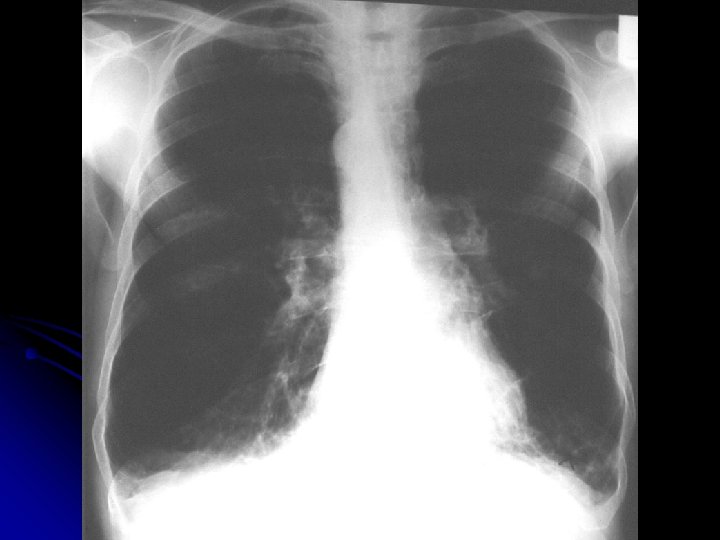

MS 76 yaşında, erkek hasta İş adamı

YAKINMASI Nefes darlığı (eforla) l Öksürük l Balgam çıkarma (mukoit) l Halsizlik l

Özgeçmiş l Kot kırıkları 4 yıl önce, travma öyküsü yok

ALIŞKANLIKLARI 50 paket/yıl sigara 10 yıldır bırakmış

FİZİK MUAYENE l l l Genel durum iyi, bilinç açık Dispne (+) Ateş: 36. 8 ‘C TA: 150/90 mm. Hg Nabız 100/dk, ritmik Kalp sesleri: S 1, S 2 doğal. S 3(-)

Solunum Sistemi l DSS: 30/dk, l l l torakoabdominal. Bilateral solunum sesleri azalmış. Ekspiryum uzun Tek tük wheezing mevcut

Fizik Muayene Dispneik Ödem Karaciğer kot kenarını geçiyor

Sorular: Bu bulgular hangi hastalıkları düşündürür? l Hangi tanı yöntemlerine başvurulmalı? l

SFT FVC: 1740 ml(%59) FEV 1: 640 ml(%29) FEV 1/FVC: %37 FEF 25 -75: 0, 22(%9)

VOLÜMLER Pletismografik TLC: 7240 ml(%136) RV: 3780 ml(%140) RV/TLC: %52

DİFÜZYON KAPASİTESİ DLCO m. L/mm. Hg/dak l DLCO/VA m. L/mm. Hg/dak /L l %26 %32

AKG Pa. O 2: 47. 2 mm. Hg Pa. CO 2: 39 mm. Hg Sa. O 2: %85 p. H: 7. 4 HCO 3: 28. 4

Hasta GOLD a göre hangi evrededir? l l HAFİF ORTA AĞIR ÇOK AĞIR